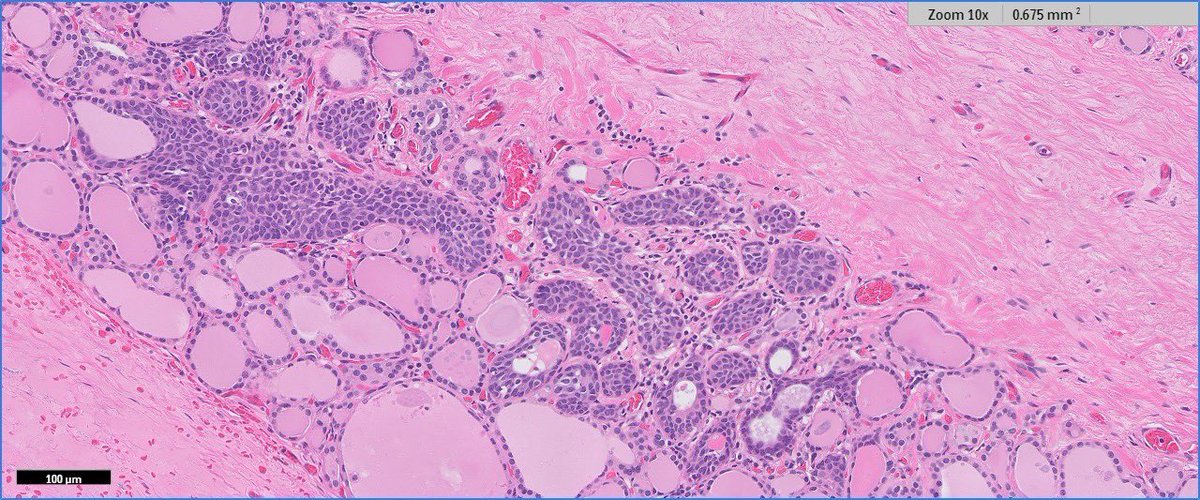

4.3 cm renal mass confined to kidney, tumor cells are predominantly with proliferative, tubular pattern 🎨 CK7 positive (strong, diffuse) 🎨 CD117 negative Thoughts? Sean R Williamson MD Kiril_T_Can Michelle_Hirsch (Donovan) Priya Rao, MD Ankur Sangoi

Kidney, young F adult #gupath Dr. Luca Olaleke Folaranmi Aurélien Morini, MD, MSc 🇫🇷🇪🇺💙💛 Celina Stayerman MD 🔻Nusrat Zahra🔻🇵🇸 @miss_me1986 Gonzalo De Toro Tristan Rutland MBBS FRCPA IFCAP Anandi Lobo, MD Sumanta Das Lorand Kis Erik Kouba bansar Carlos Miguel Ruiz Carlos Nieves Padma Priya J Susan Prendeville @AkgulMd Ankur Sangoi Barry McGinn